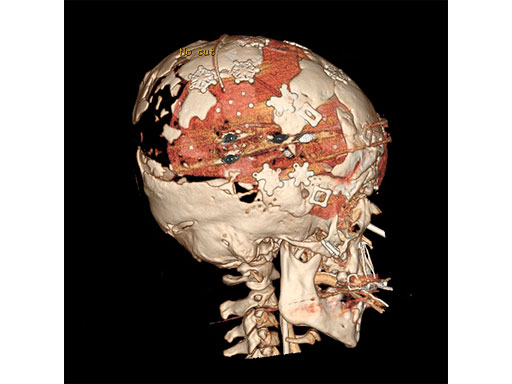

An 8-year-old girl with Apert Syndrome (Fig 5) was examined after being treated at another institution. The cause for loss of cranial bone was unknown. An anterior and posterior cranial expansion was given to treat the increased intracranial pressure.

After that healed, a simultaneous PSI cranioplasty and Le fort II osteotomy with zygoma repositioning were performed. The PEEK implants were fixated using MatrixNeuro ULP implants (Fig 6). A midface distraction device was then mounted on the PSI implants and distracted the Lefort 2 segment to treat the patient's sleep apnea (Fig 7).